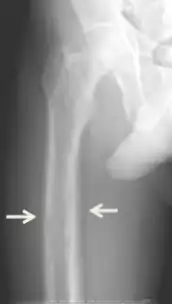

Non-specific symptoms include feeling tired and thirsty, mood changes including, feeling blue, weak and irritable along with other symptoms like itching, headache, joint pain, forgetfulness and abdominal pain have also been noted.[8][4][9][1] More specific symptoms related to elevated blood calcium and phosphate levels include bone pain or osteodynia and tenderness which are common and related to proximal muscle tenderness. Other signs can include pancreatitis, kidney stones, corneal calcifications, thinning of long bones, and hypodermic calcifications which may be palpable in some patients.[2][4][1]

Conditions due to bone loss such as osteopenia and osteoporosis are common in tertiary hyperparathyroidism along with pathologic fractures. Pseudoclubbing of the digits can also be indicative of a severe tertiary hyperparathyroidism due to excess resorption at the distal phalanges.[8][1]

Diagnosis includes both clinical and laboratory investigations. Radiological investigations include looking for signs of bone loss in both the hands and pelvis which is characteristic of tertiary hyperparathyroidism.[8] Other clinical examination can include grading of muscle weakness, which is done by asking the patient to stand from a seated position with their hands folded across their chest.[4][8] Laboratory investigations include evaluating blood calcium and alkaline phosphatase, which are always increased in tertiary hyperparathyroidism. Other common results from laboratory investigations would include decreased vitamin D levels, elevated blood parathyroid hormone and hyperphosphatemia.[9][8][1][4]